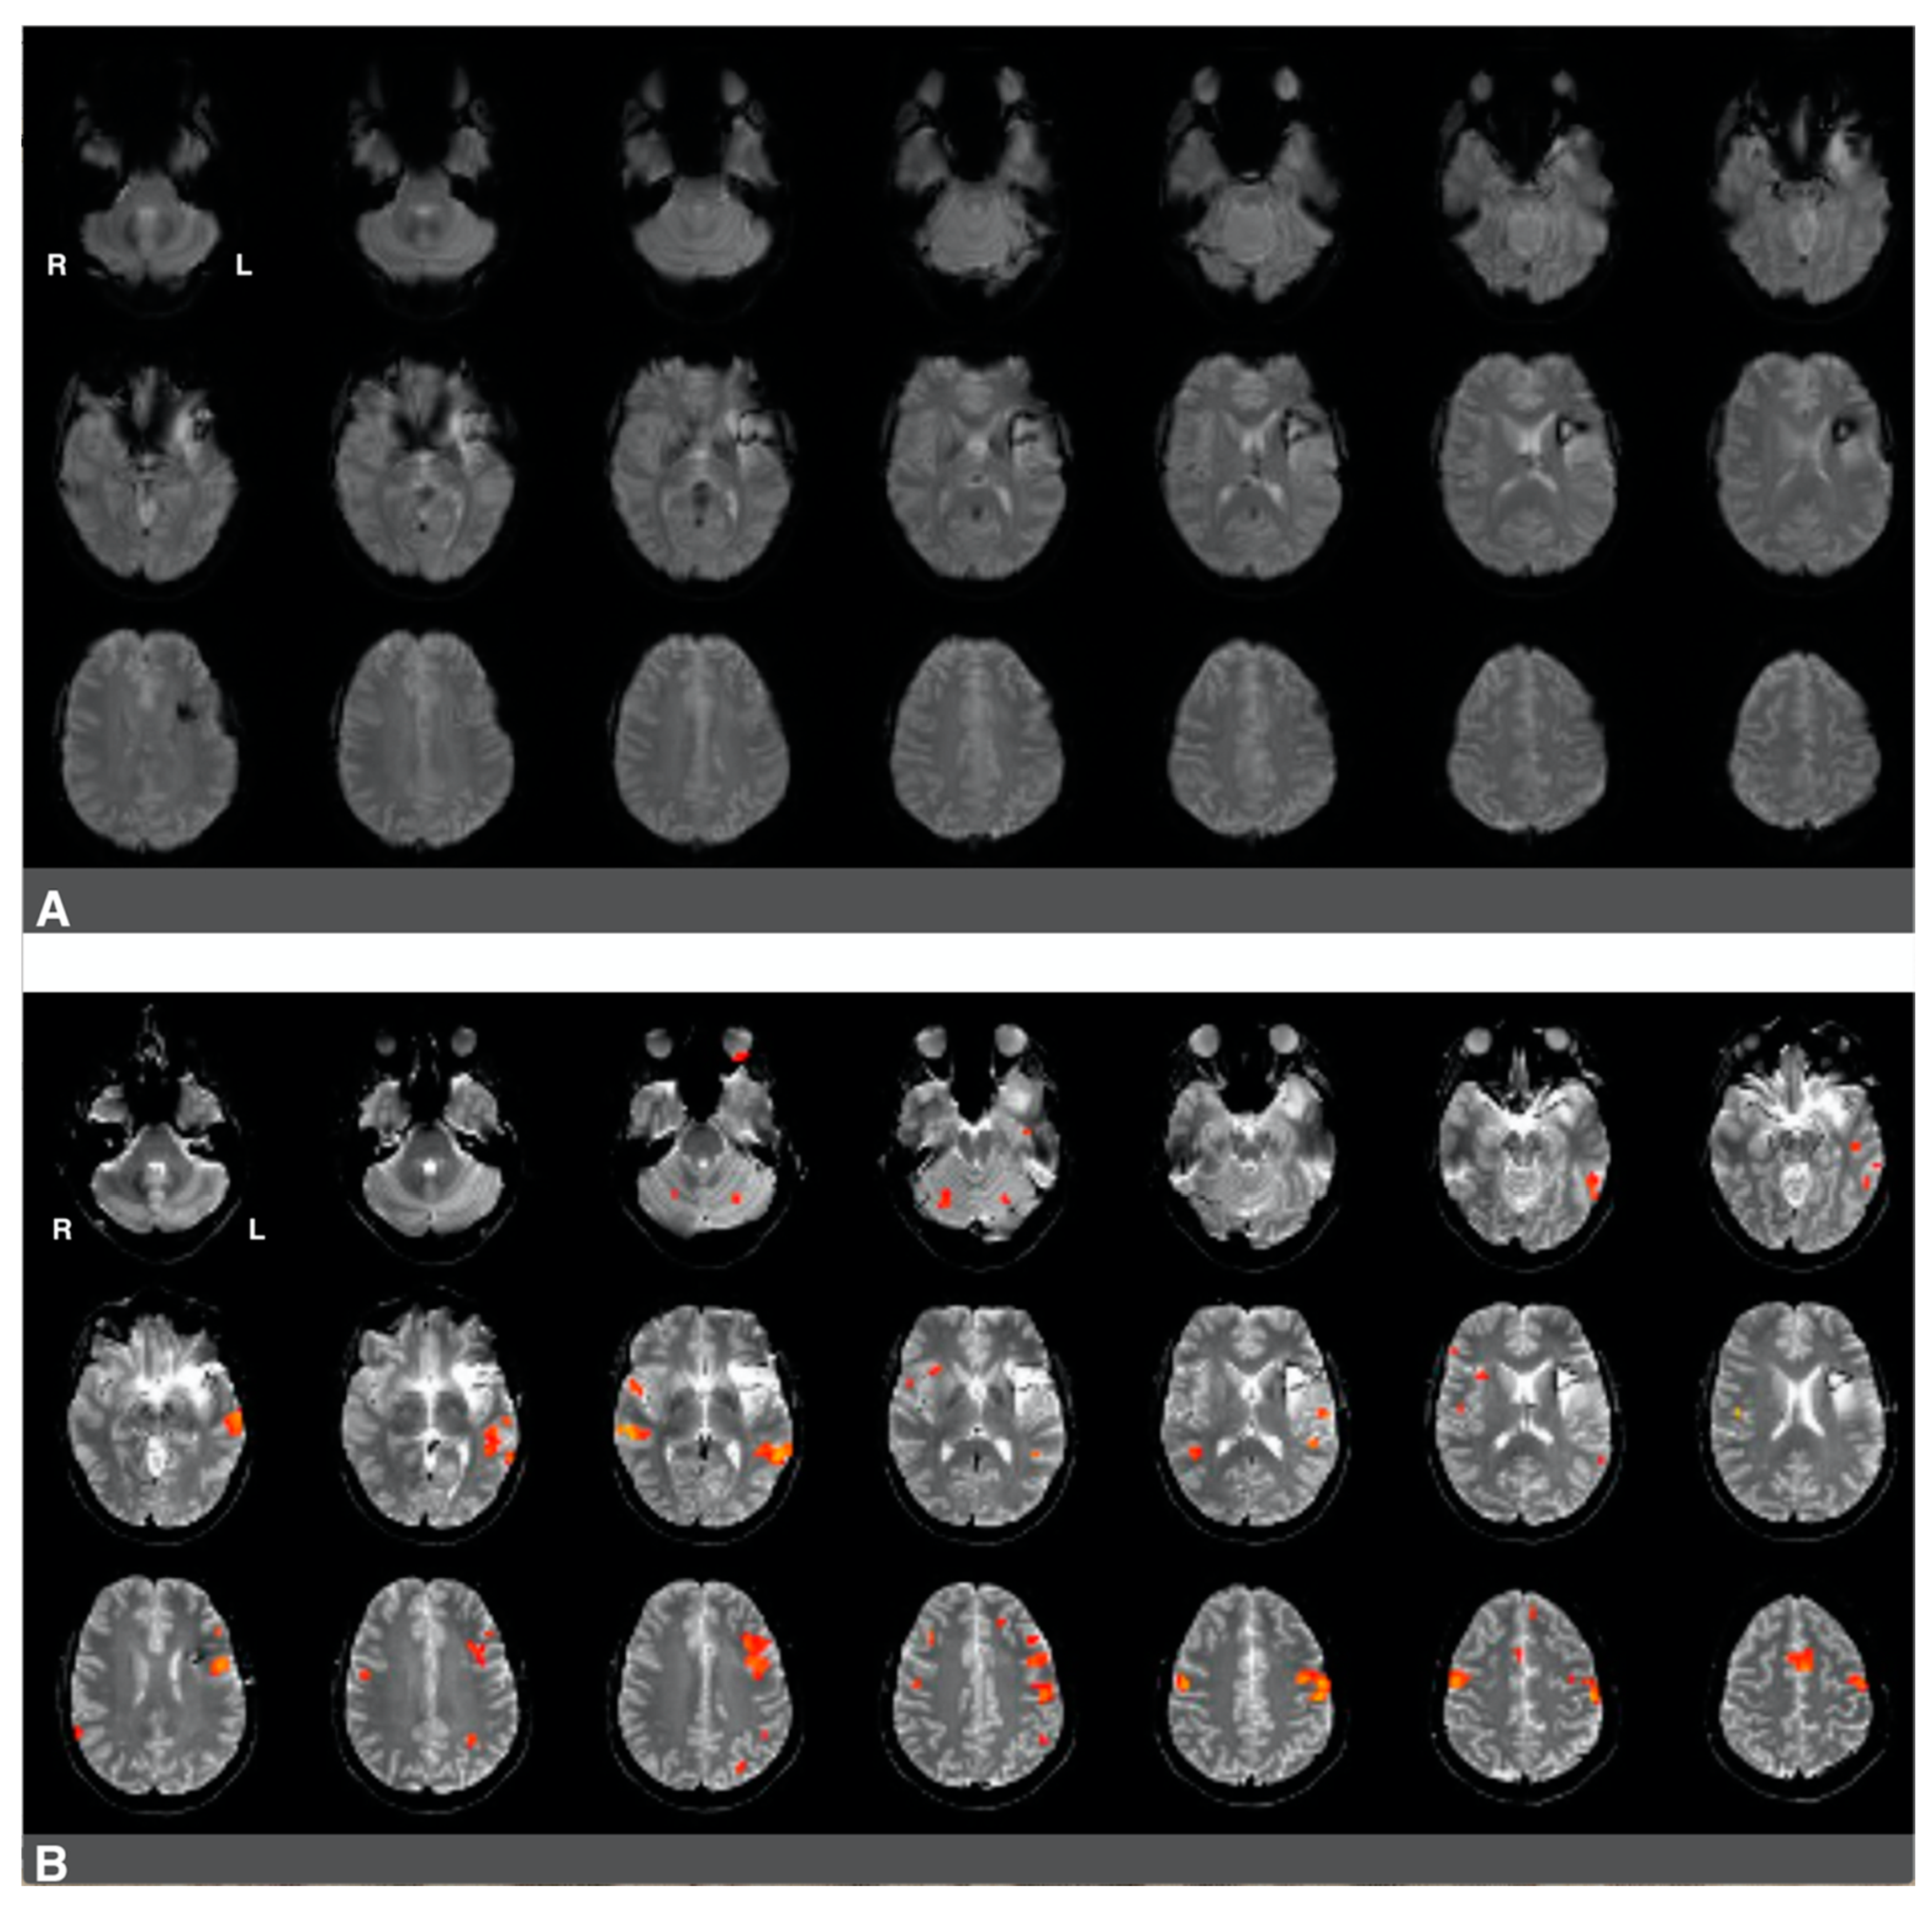

3.2. The Impact of Brain Surgery on Active Voxel Counts and Language Laterality